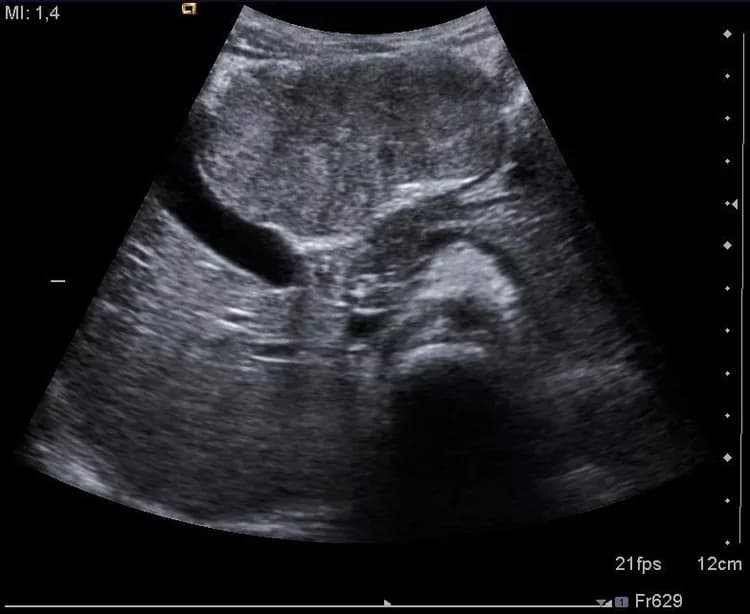

Watch this slideshow on Focal Nodular Hyperplasia of the Liver and learn about a condition that results in a benign tumor growth in the liver.